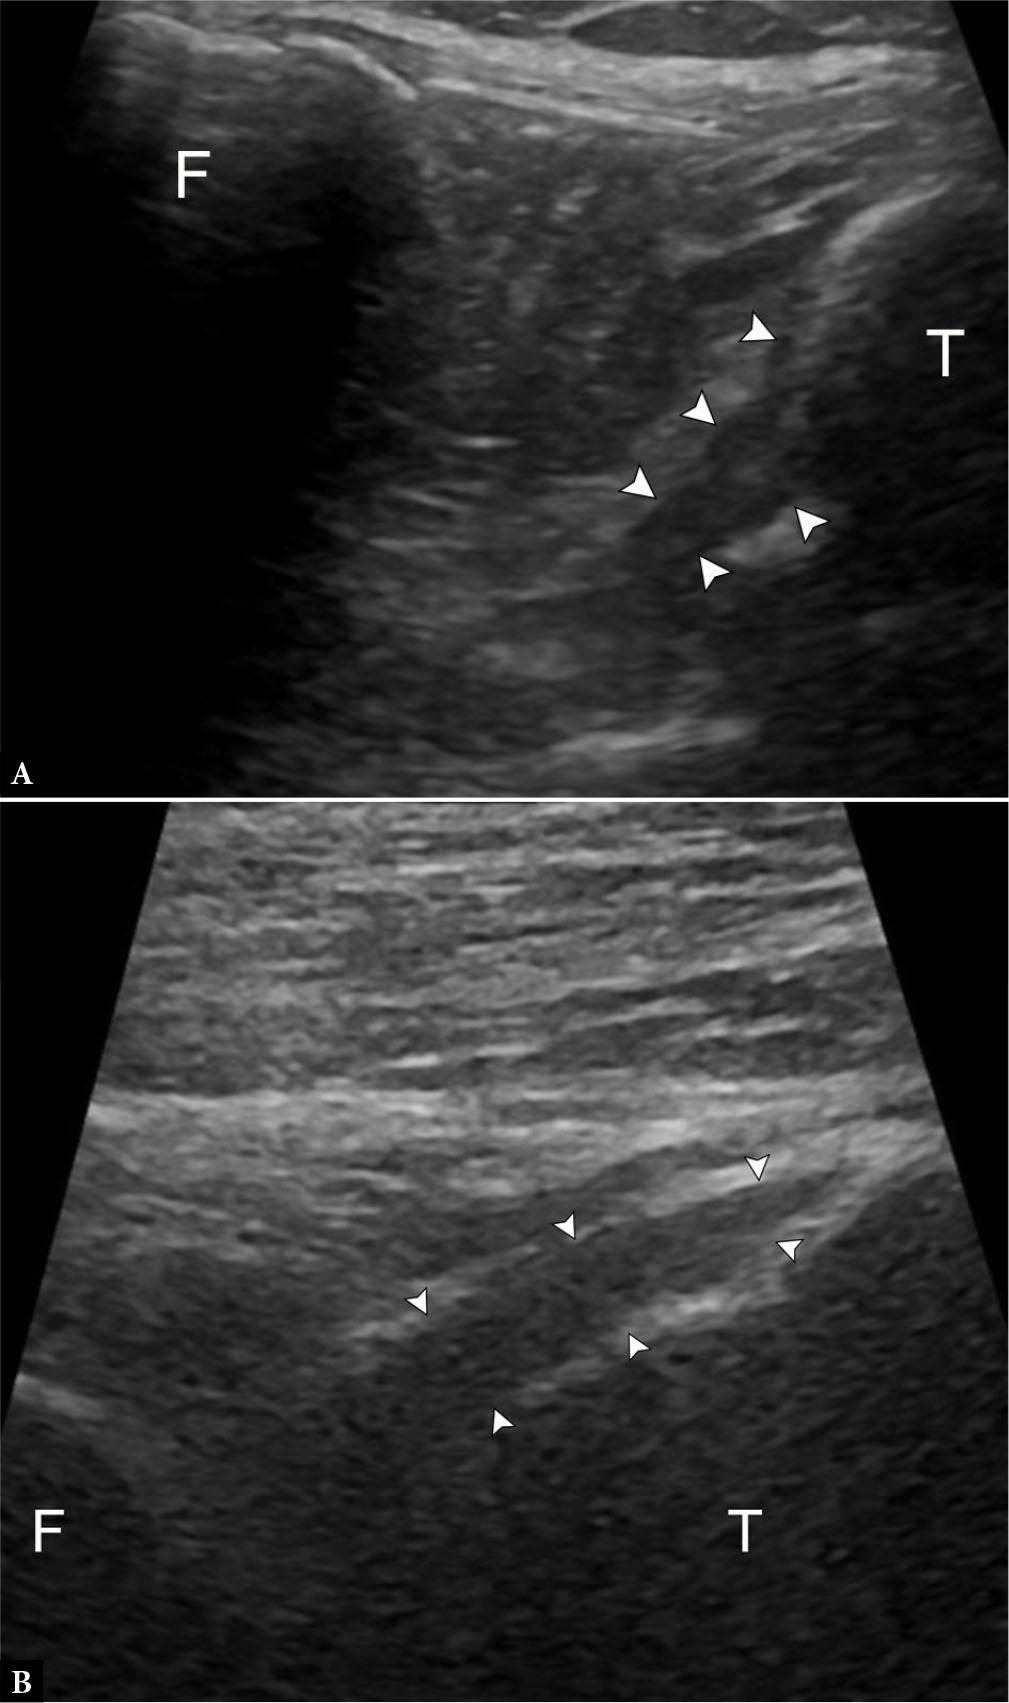

Fig. 10.

75-year-old female with high-grade partial fibular collateral ligament (FCL) injury. A. Longitudinal grayscale US image along the course of the FCL (arrowheads) next to the femoral popliteal groove (F) and tibial plateau (T) demonstrates attenuated remnant fibers with surrounding fluid (arrow). Compare to the normal appearance of the FCL on longitudinal grayscale US image B. with anisotropy (curved arrow) at the proximal portion